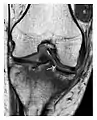

Fatigue fractures are more frequent in women which may be due to the relatively smaller bones of women. Moreover, pregnancy is a well-recognized risk factor for femoral neck fatigue fracture. While fibular and metatarsal fractures have a low risk of complications, other sites including the femoral neck, midanterior tibia, navicular, talar, and other intraarticular fractures are prone to complications such as delayed union, nonunion, and displacement. The site of the insufficiency fracture may be specific to the activity: for example, rugby and basketball players are more prone to navicular fractures, while gymnasts have a higher risk for talar fractures (Figure 7). Long distance runners are at increased risk for pelvic, tibial (Figures 8 and 9), and fibular fractures. In the military, calcaneus (Figure 10) and metatarsals are the most commonly cited injuries, especially in new recruits. Billiard players are at risk for upper limb fractures (Figure 11).[1]

Figure 7: Fatigue fracture of the talus in a 25-year-old male basketball player with right hind foot and ankle pain, without history of trauma, and a normal initial radiograph (not shown). (a) One-month followup lateral radiograph shows normal appearance. (b) Sagittal T1-weighted MRI shows an irregular fracture line (arrow) within an ill-defined area of hypointensity corresponding to bone marrow edema.[1]